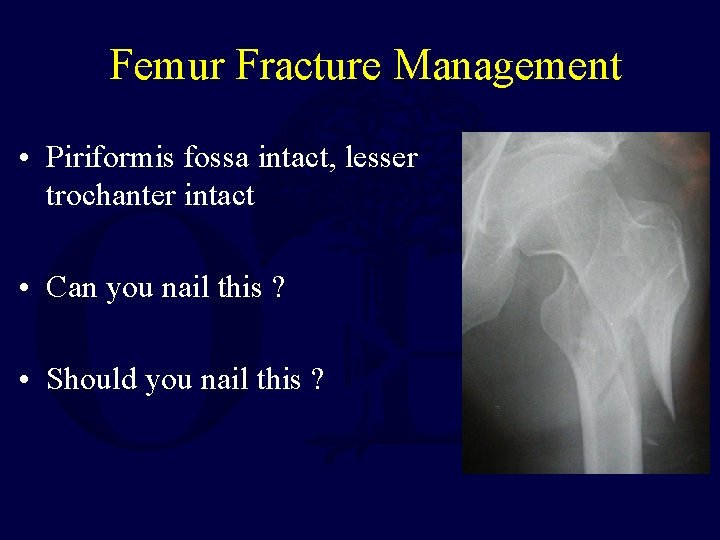

Femur Fracture Management • Piriformis fossa intact, lesser trochanter intact • Can you nail this ? • Should you nail this ?

Femur Fracture Subtrochanteric Fracture Management • Possible to perform intramedullary nail if the piriformis fossa is intact • Choice of nail type depends on if the lesser trochanter is intact • Varus seen with proximal femur intramedullary nailing • Plating is also an option with/without an intact starting point